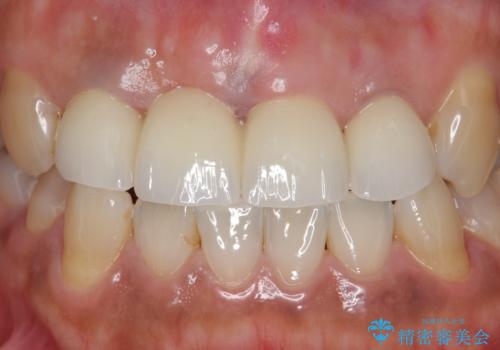

- オールセラミッククラウン(スペシャル)…¥130,000×4、仮歯…¥10,000×4、ファイバーコア…¥20,000×3、精密根管治療費別途費用は治療当時の料金となります

前歯の補綴ではオールセラミッククラウンを希望される患者様が多いですが、オールセラミッククラウンの中でも、エコノミー、スタンダード、スペシャル、エクセレントとランクがあります。

その中でも特に審美性が高いのがスペシャル、エクセレントです。スペシャル、エクセレントは口腔内写真をもとに熟練の技工士が、患者様の口腔内に合わせたオーダーメイドのクラウンを製作致します。